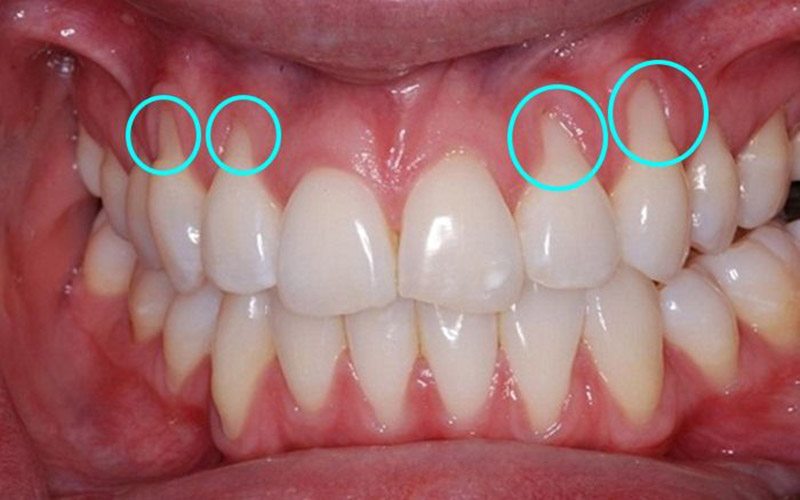

Hình ảnh viêm nha chu

Viêm nha chu

Với viêm nha chu, nướu và xương bị tiêu đi, tạo thành các túi ở chân răng. Chân răng ngày càng lộ ra ngoài. Các mảnh vụn tích tụ trong khoảng trống giữa nướu và răng, gây nhiễm trùng khu vực này. Hệ thống miễn dịch tấn công vi khuẩn khi mảng bám lan ra bên dưới đường viền nướu vào các túi. Điều này dẫn đến một phản ứng miễn dịch, liên quan đến việc giải phóng độc tố và viêm nhiễm, khiến xương và các mô liên kết neo giữ răng bắt đầu bị phá vỡ. Răng có thể bị lung lay và rụng. Những tổn thương do viêm nha chu gây ra không thể khắc phục.